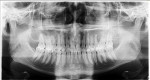

A 32-year-old healthy man, referred by his general dentist, presented with mild numbing sensation symptoms on the left aspect of his maxilla. Four months before the referral, when the patient had no symptoms, a panoramic radiograph revealed the splaying of teeth. Possibly because of the superimposition of radiopaque structures, this went unnoticed. Upon the author's clinical examination, a CBCT revealed a well-defined, multilocular radiolucent lesion present between teeth Nos. 13 and 14. The general behavior of the lesion was rather aggressive. Biopsy results confirmed ameloblastoma, a common benign tumor of the jaws that requires marginal resection due to its high recurrence rate. A treatment plan with the surgical and restorative team was presented to the patient. The treatment would begin with a hemimaxillectomy with secured margins and mucocutaneous fibula graft with implant placement at the time of resection. After 6 months of healing, the second-stage surgery would follow with the insertion of a 3D-printed long-term temporary restoration. Several months later, after occlusion changes and complete healing, the final prosthesis would be inserted. The case was completed in 12 months using a digital workflow plan (DEXIS, dexis.com) that involved the use of intraoral scanning, virtual surgical planning (VSP) software, advanced imaging, exocad software, 3D printing, and more.